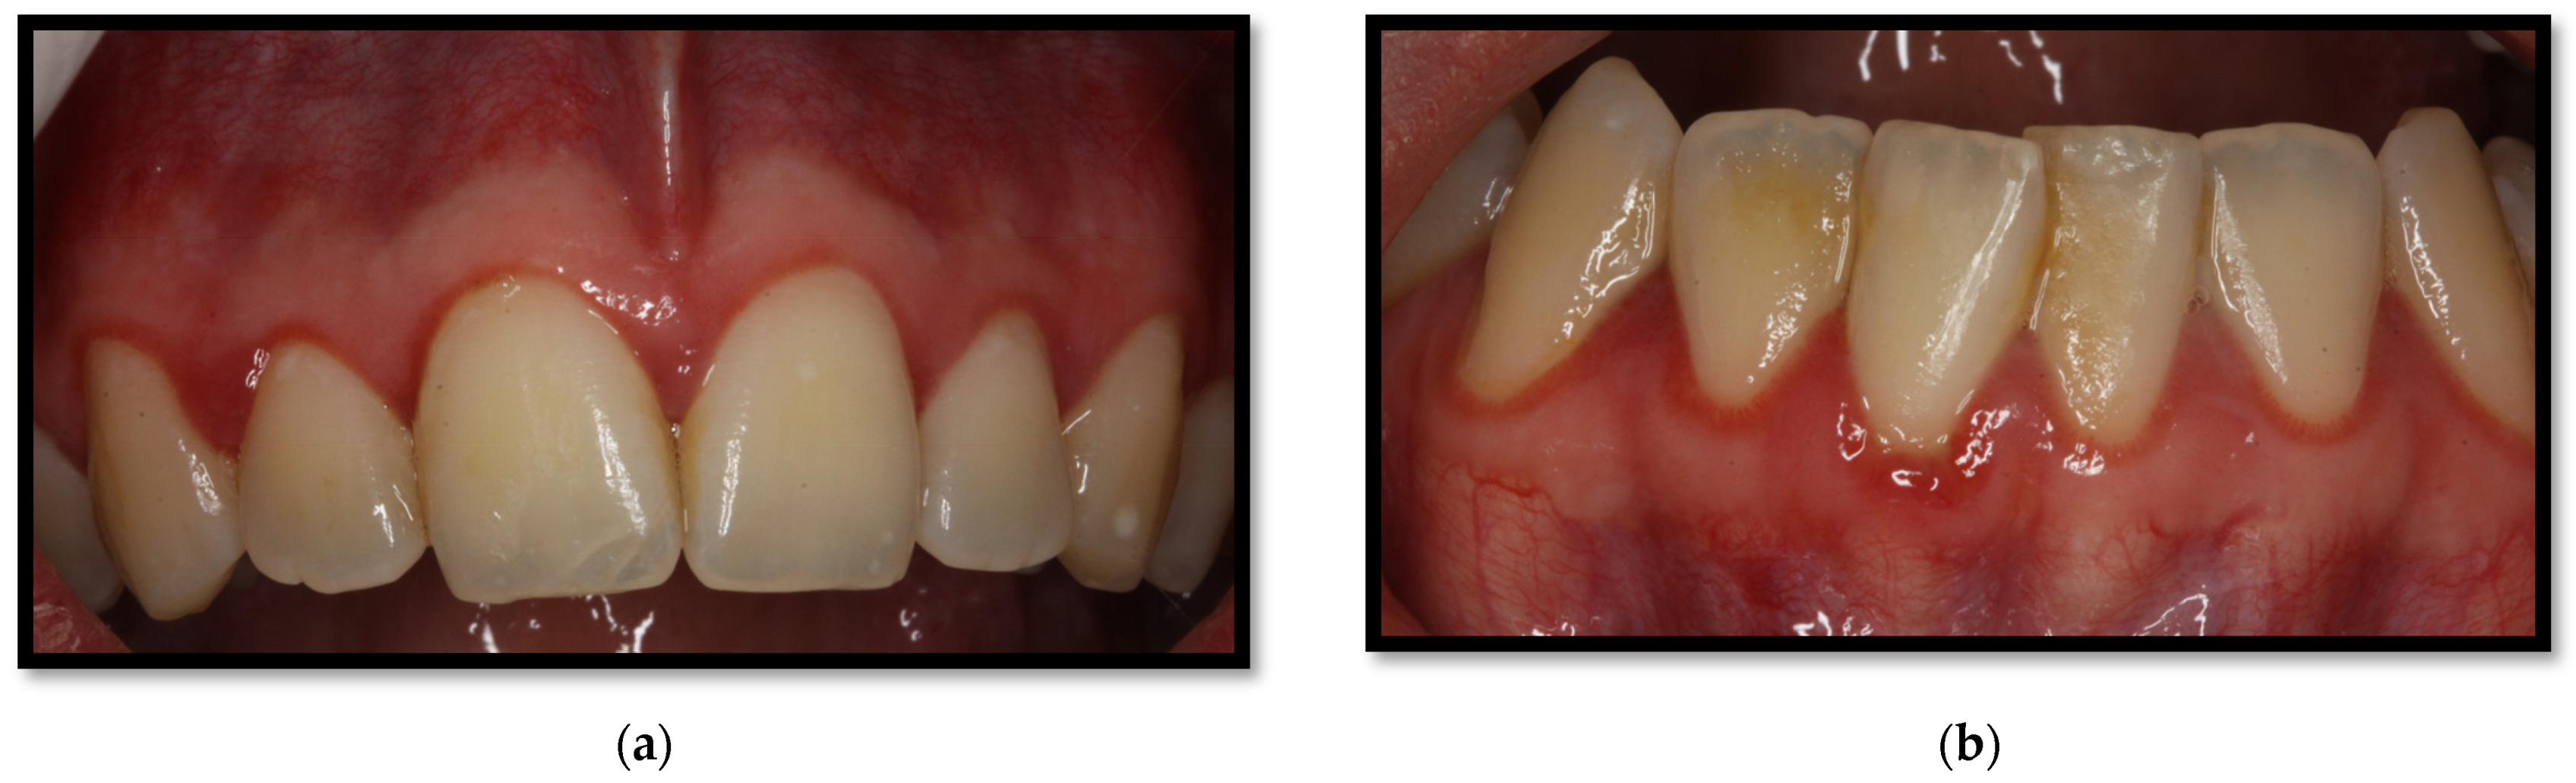

Periodontitis is characterized by microbial association within a dental biofilm, as well as host-mediated inflammation, which triggers the destruction of tissue supporting the teeth [27]. Its clinical manifestation includes gum inflammation, bleeding-prone mucous membranes, periodontal pouch formation, loss of clinical insertion, plaque, as well as supragingival and subgingival stone formation. In more severe cases, even dental displacement might develop, as well as pathological dental migration (Figure 5a,b) [27,28]. In HIV-positive patients, the dental biofilm usually has a relevant microbial heterogeneity, involving unusual bacteria within the oral cavity, such as P. aeruginosa, A. baumannii, E. coli, among others [18,20], as well as diverse Candida spp., encompassing C. albicans, C. glabrata, C. krusei, C. tropicalis, and C. dubliniensis. The presence of these microorganisms has been correlated to ART and a CD4+ T lymphocyte count of <200 cells/μL [9]. Some risk factors triggering periodontitis include passive tobacco consumption, diabetes, CD4+ T lymphocyte count <200 cells/μL, and xerostomia, among others [16,27].

Figure 5.

(a) Upper and lower arch chronic periodontitis (b) Anteroinferior sextant chronic periodontitis.